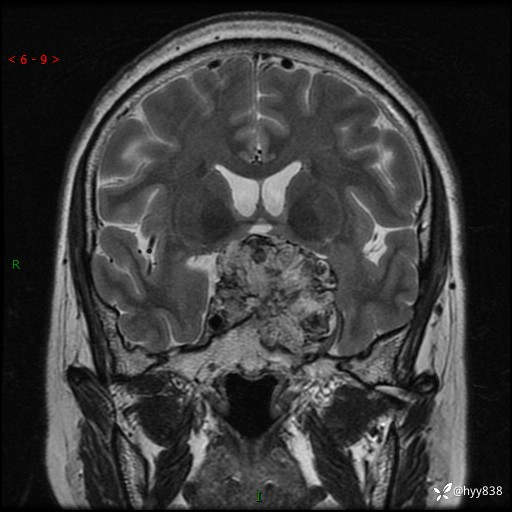

T2WI

鞍区MRI平扫

临床诊断:鞍区肿物